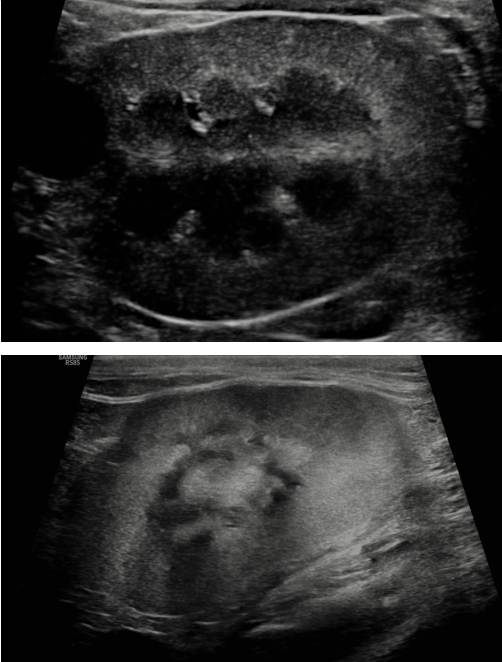

Imaging

- ์นผ์์ด ๊ณผ๋ํ๊ฒ ๋น ์ ธ๋๊ฐ๋ ์ด์์ด

- ์ ์ฒด์ ์ผ๋ก ๋ผ ๋ฐ๋ ๊ฐ์ ์์

- ์๊ตฌ ์กฐ์ง mineralization

- ์ด์ํ๋ง์ผ๋ก๋ 1/2๊ธฐ ๊ตฌ๋ถ ์ด๋ ค์